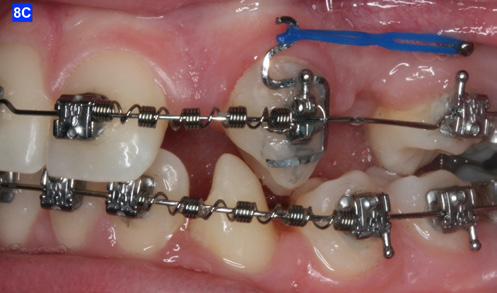

Finally, after 21 months of treatment, the patient and the parents consented to the odontectomy of the maxillary first bicuspids. The informed consent forms for the extractions and placement of TADs were signed by the parent, and all questions were answered. Risks, benefits, alternatives, and the result of no treatment at all were reviewed. Immediately after the odontectomy of #14(5) and #24(12), 1.6 x 8.0 mm AnchorPro (OrthoOrganizers) TADs were placed just mesially to the maxillary second bicuspids.6 In office power arms (a .018 x.025 SS) were fabricated and bonded to the buccal surface of the maxillary cuspids, just above the bracket.7 The purpose of the power arm is to place the applied force as close to the center of resistance of the tooth as possible. In this manner the line of action (power hook to the TAD) is parallel to the occlusal plane. The source of the force is an EC, and it must be replaced at least bi-weekly. Both arches had a .018 SS arch wire. There was a small off-center bend (tip-back, gable bend) “V” pointing occlusally, mesial to the maxillary second bicuspids.8 The purpose of this bend is to keep the roots parallel during the translation of the cuspids. There was a small OCS between #21(9) and #23(11) to shift the maxillary midline to the right. Another OCS was placed between #32(23) and #34(21) to facilitate the alignment of the mandibular left cuspid (Figure 8-A, B, C, D).

To prevent a disto-lingual moment (rotation) of the maxillary cuspids we attached PC from the lingual button on the cuspids to the framework on the hyrax. The anterior portion of the Hyrax was cut off and the remaining portion served as a TP arch for posterior anchorage. At this point, we were 25 months into treatment (Figure 9-A, B, C, D). The hyrax was removed after 30 months of treatment.

Figure 8A: TADs in situ, frontal view 8B: TAD in situ, right lateral view 8C: TAD in situ, left lateral view 8D: Power arms Figure 9A: Maxilla, occlusal view 9B: Maxilla, occlusal view 9C: Maxilla, occlusal view Figure 9D: After the removal of the Hyrax, occlusal view Figure 10A: Center bend “V” pointing gingivally Figure 10B: OCS between the cuspids and the central incisors Figure 10C: Composite build-ups on the mandibular first molars Figure 10D: Adrian “U” bend spring